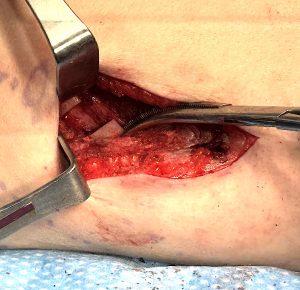

The overlapping bone segment is excised, and the rib is stabilized using a four-hole rib fixation plate with two self-drilling 7-mm screws on each side.